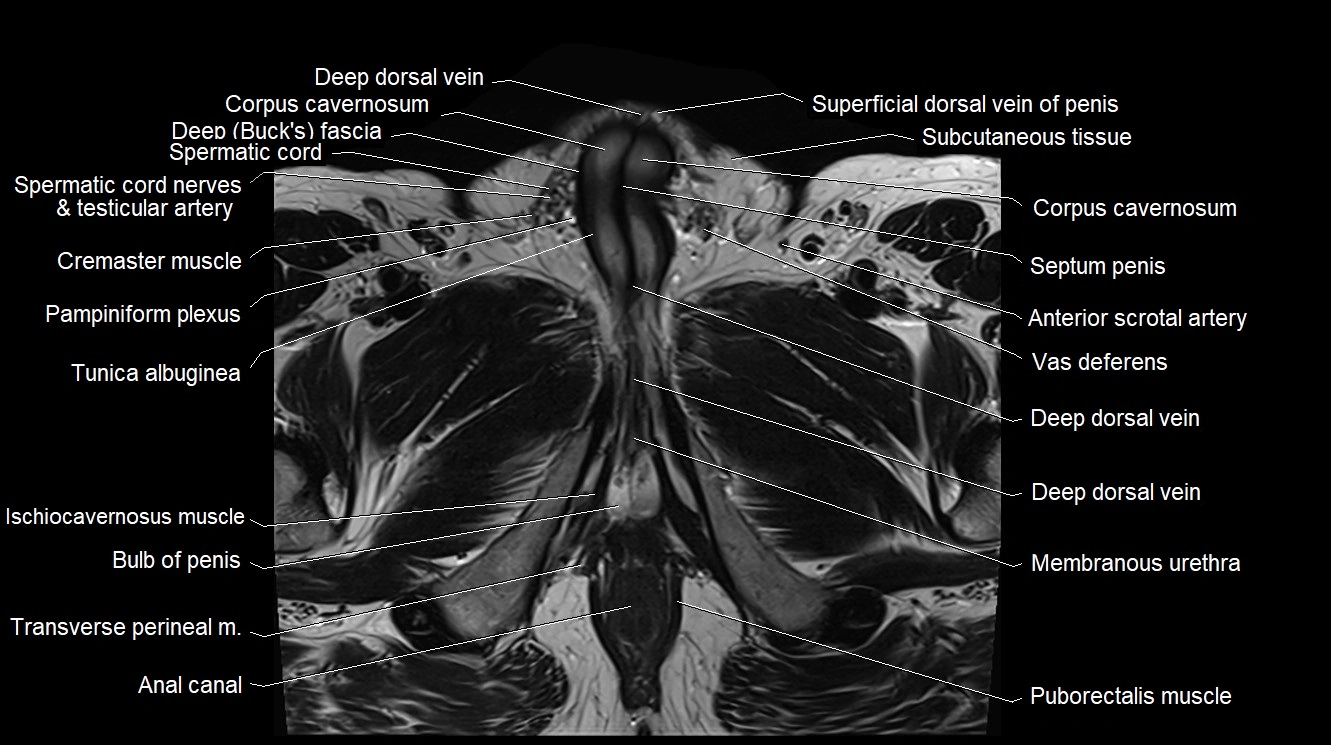

- Anal canal

- Bulb of Penis

- Corpus cavernosum

- Cremaster muscle

- Crus of penis

- Deep dorsal vein of penis

- Deep dorsal vein of the penis

- Membranous urethra

- Pampiniform plexus

- Puborectalis muscle

- Spermatic cord

- Spermatic cord nerves

- Transverse perineal muscle

- Tunica albuginea (penis)